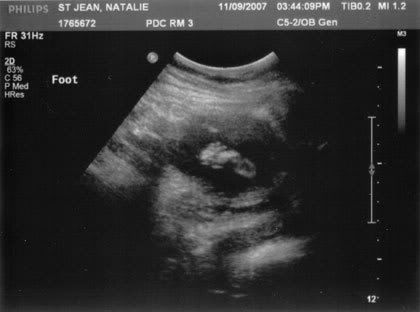

Baby’s first footprint :D

So then she started measuring the legs, got a photo of a foot sticking out, measured the spine. And every time she scanned back and forth his legs were wide open, showing off his boy parts. The tech actually apologised, “Sorry! Can’t help it, he has it all on display!” I just laughed.